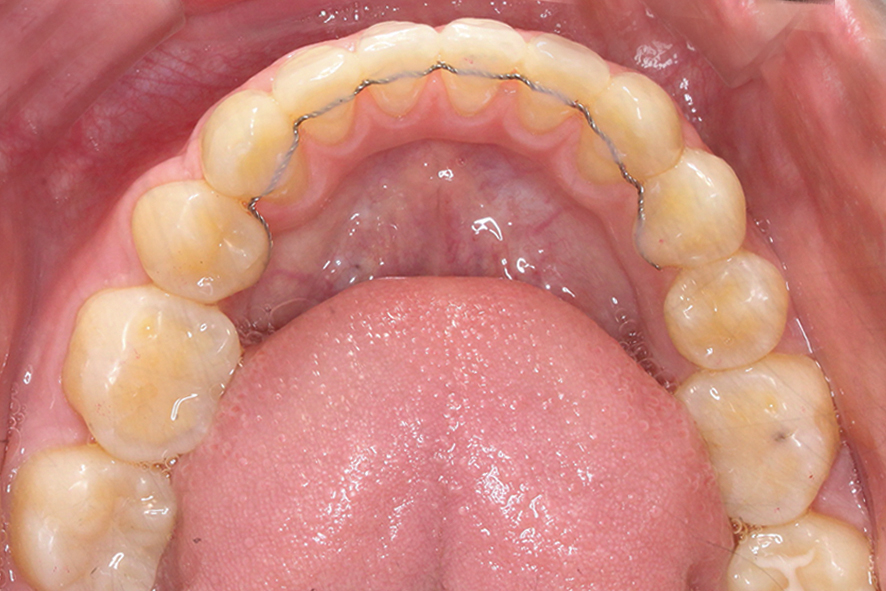

하악의 경우 상악보다 상대적으로

안모의 길이가 짧고 악궁의 길이도

길지 않은 모습입니다.

다만 치열의 정중선이 한쪽 방향으로

치우쳐져 있기 때문에 데이몬교정을 통해

안모의 정중선을 바르게 맞추어야 할 것으로 보입니다.

하악 또한 입돌출 교정 후 치열이

가지런해지고 안모의 정중선도

거의 맞춰진 모습인데요,

상악보다 악궁의 길이가

짧았기 때문에 과도한

치아의 이동은 하지 않은 모습입니다.